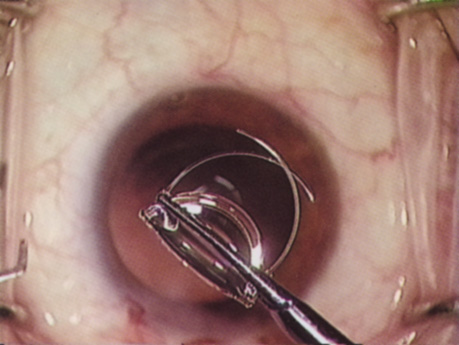

Capsulorrhexis can be performed with a cystitome, capsulorrhexis forceps, or combination-type instruments. Regardless of which instrument is used, several principles can help the surgeon successfully complete capsulorrhexis. It is important to maintain the anterior chamber, because making the chamber shallow increases tension on the zonules and causes the tear to run peripherally. The authors recommend the use of a viscoelastic agent for maintaining chamber depth and, of course, for endothelial protection. Therefore, if the tear begins to run peripherally, the surgeon should redeepen the anterior chamber before attempting to redirect the tear. Additionally, folding the capsule margin can aid the surgeon in redirecting the tear more accurately (Fig. 10).

Fig. 10. The capsulorrhexis tear is more easily redirected by folding the capsule over, in advance of the tear.